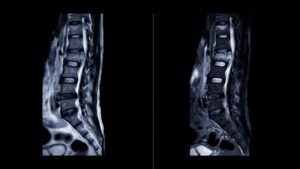

Как изглежда остеохондрозата на MRI

MRI изследването е едно от най-често използваните образни изследвания за оценка на дегенеративните промени в гръбначния стълб.

При остеохондроза на MRI могат да се наблюдават:

намалена височина на междупрешленния диск

промени в структурата на диска

дегенеративни промени в съседните прешлени

образуване на остеофити (костни шипове)

промени във фасетните стави

Образните изследвания дават важна информация за състоянието на гръбначния стълб, но винаги трябва да се интерпретират заедно със симптомите на пациента.